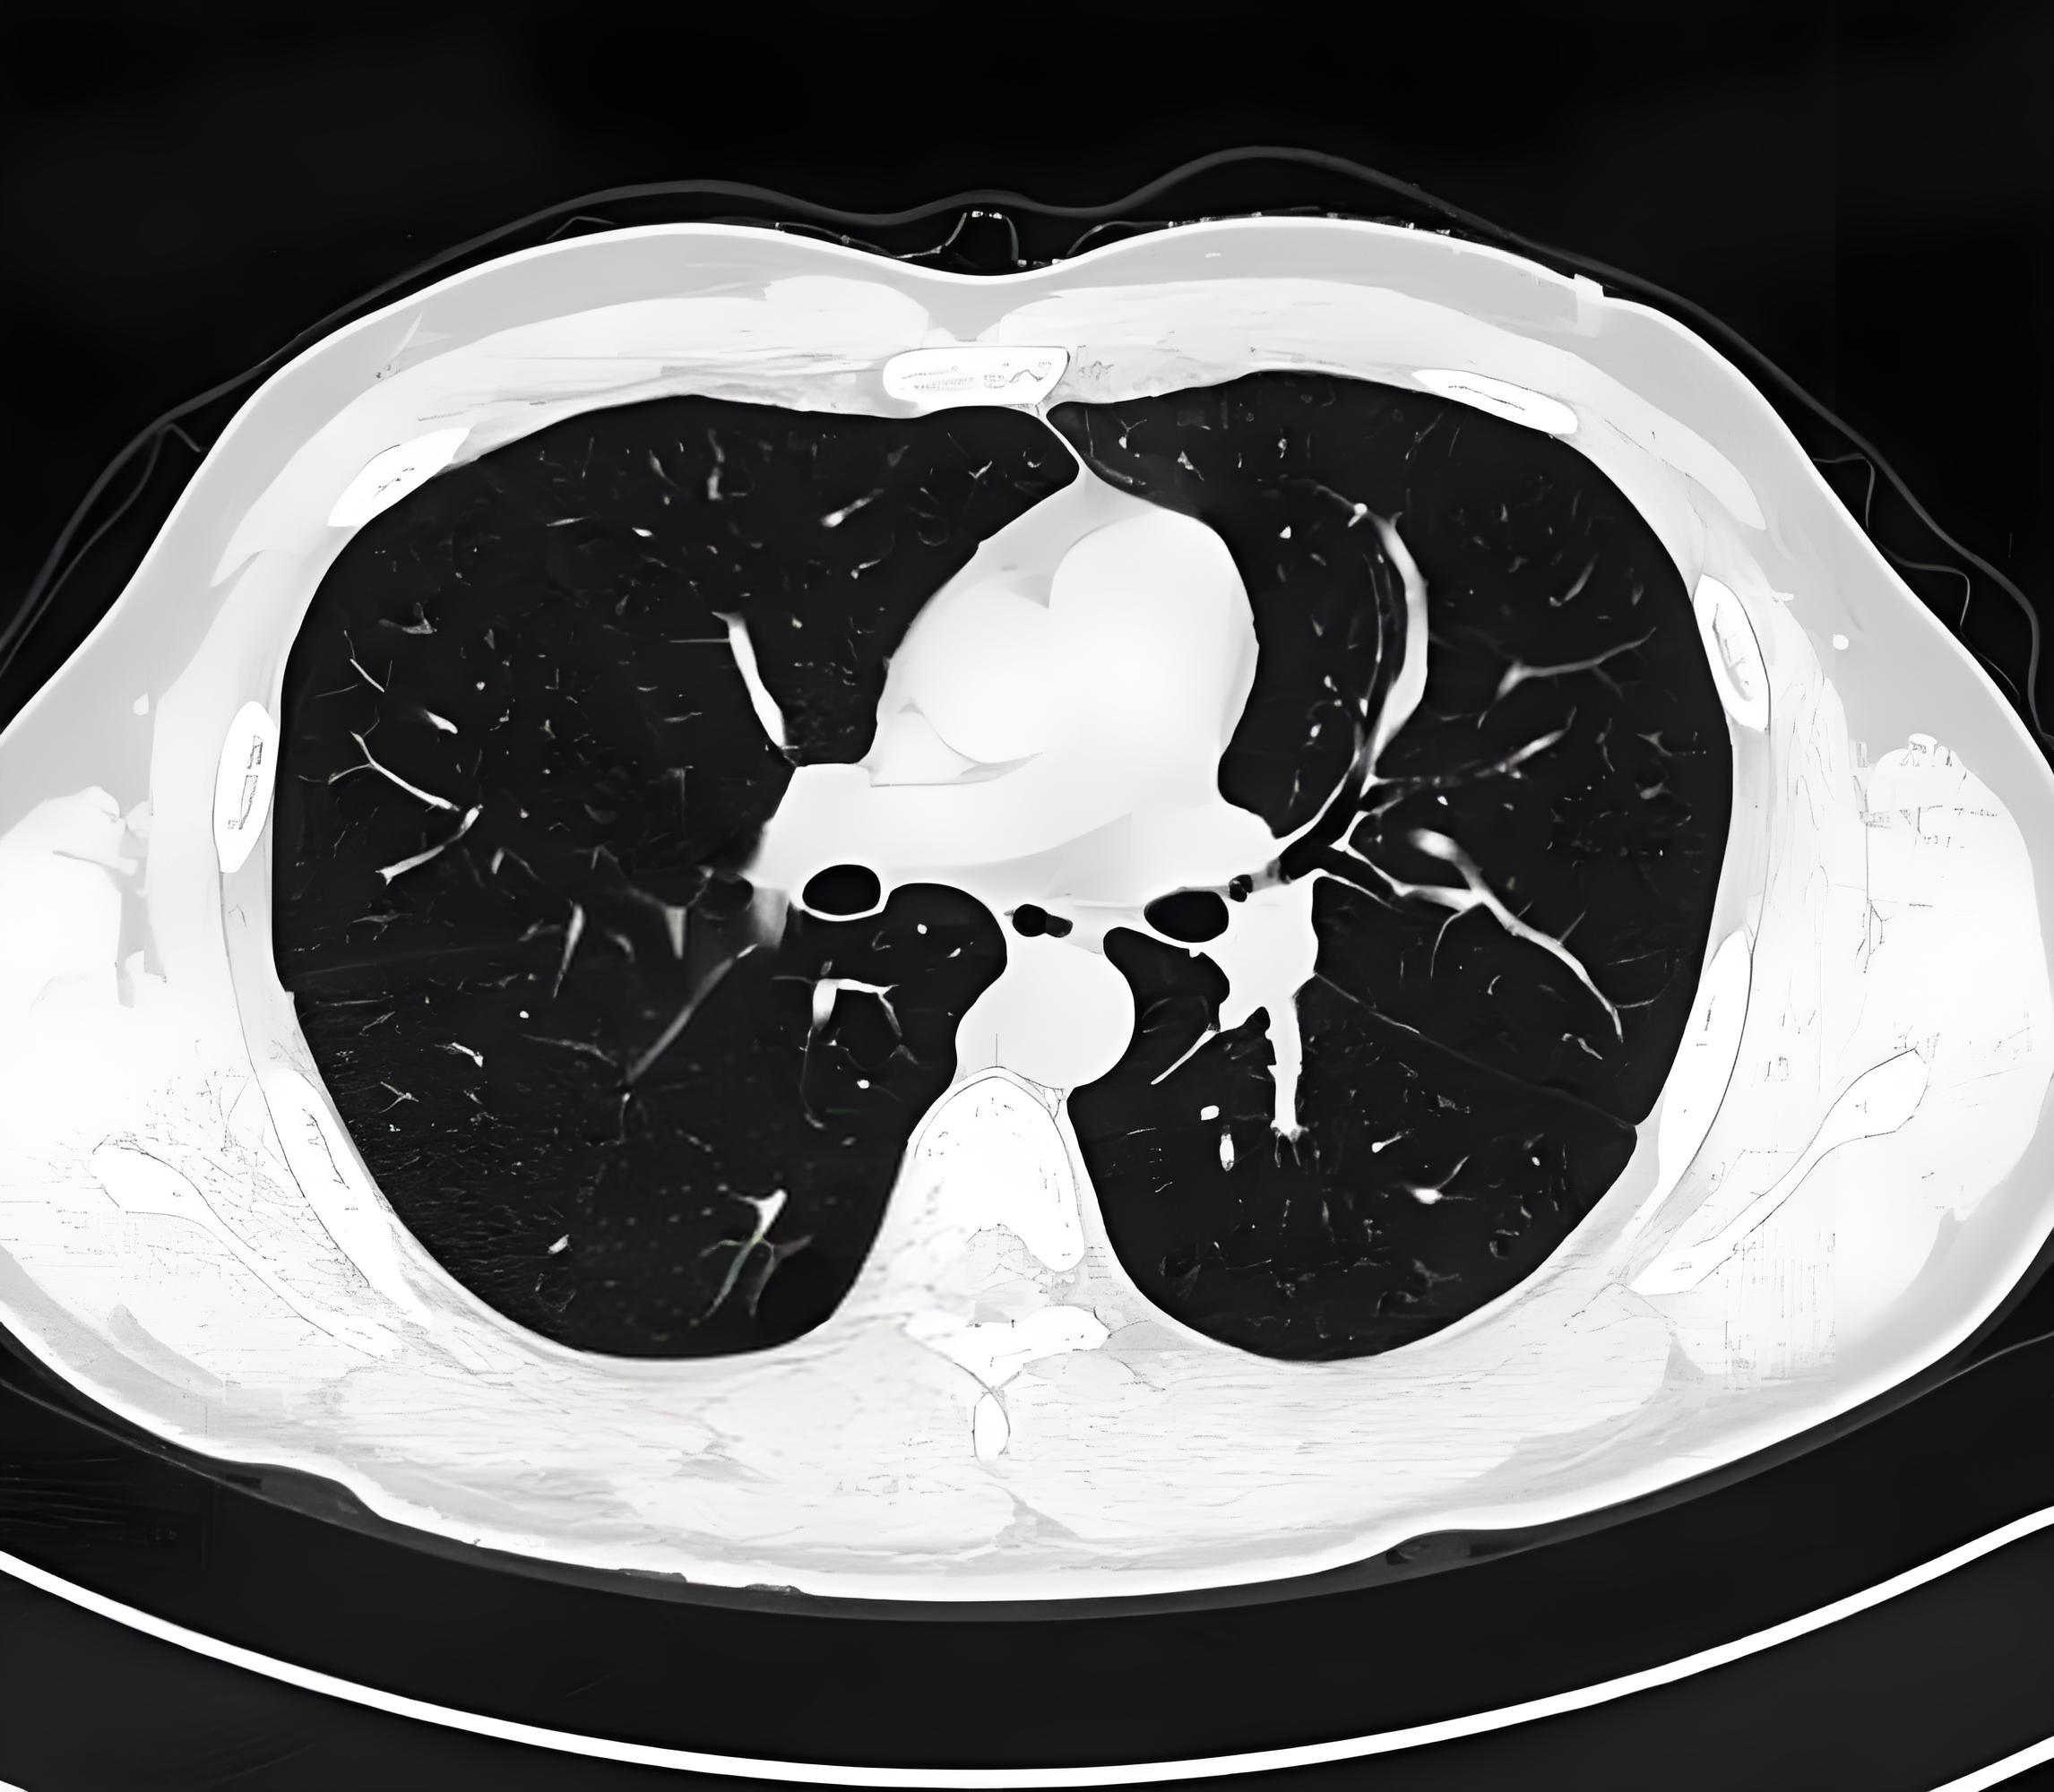

ct肺纹理增多

肺纹理增多:如同墙壁上的细小纹路,常见于长期吸烟者,工作环境差或